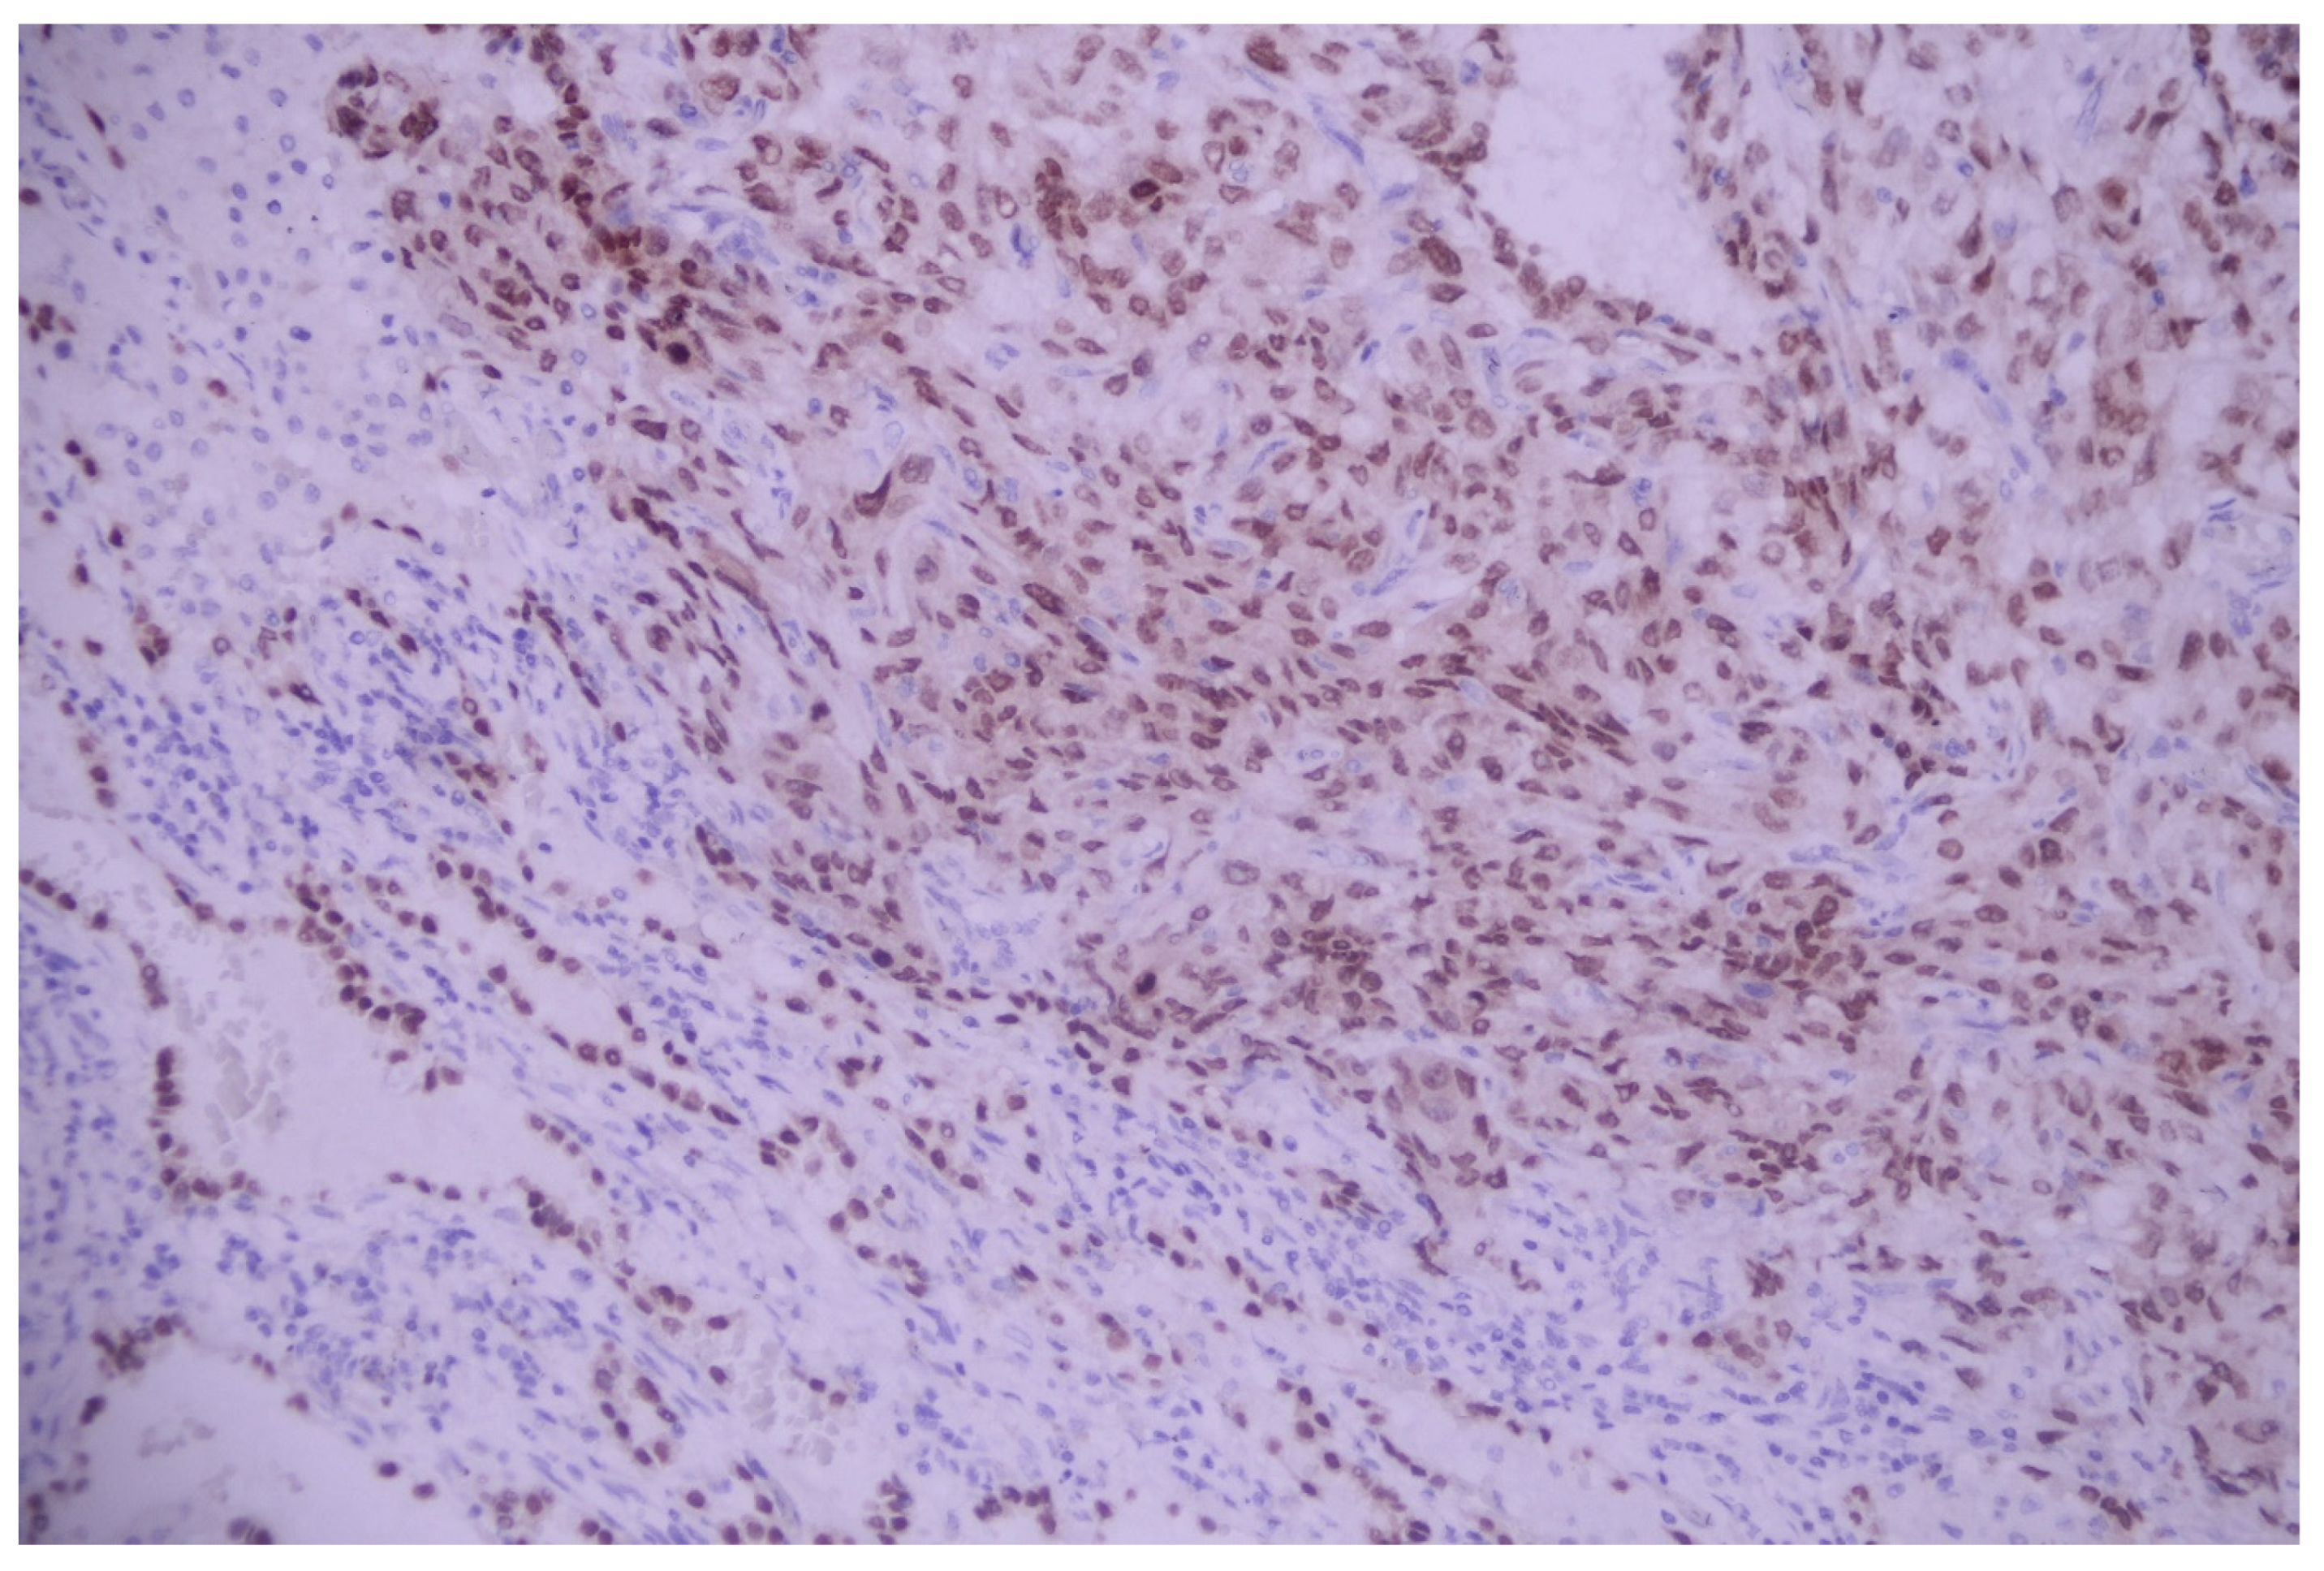

3.1. Case No. 1

3.2. Case No. 2

3.3. Case No. 3

3.4. Case No. 4